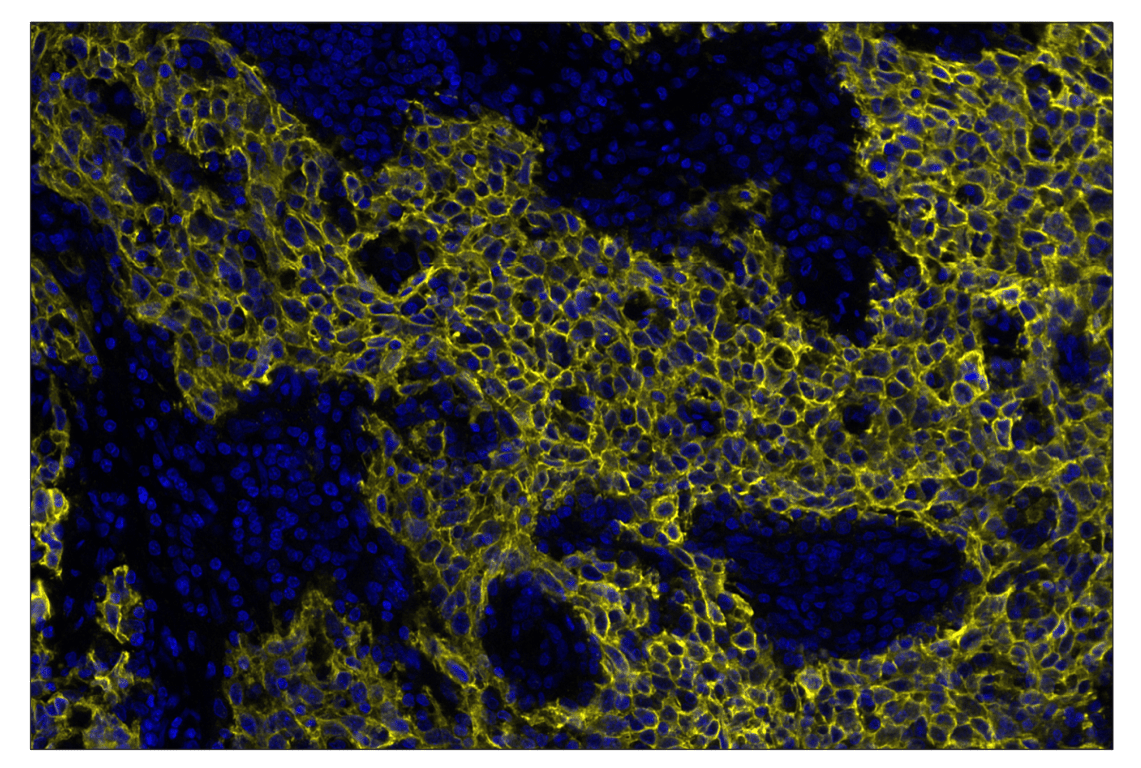

SignalStar™ multiplex immunohistochemical analysis of paraffin-embedded human squamous cell carcinoma of the cervix using TACSTD2/TROP2 (F4W4J) & CO-0150-594 SignalStar™ Oligo-Antibody Pair #90680 (yellow) and DAPI #4083 (blue). All fluorophores have been assigned a pseudocolor, as indicated.

Immunohistochemistry Image 2: TACSTD2/TROP2 (F4W4J) & CO-0150-488 SignalStar<sup>™</sup> Oligo-Antibody Pair